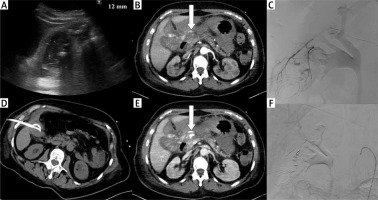

Photo 1

Complication. Acute calculous cholecystitis with infiltration of the gallbladder wall on ultrasound examination (A). Cholecystostomy was indicated due to pneumonia and performed using the transabdominal approach (B). 8 days after the procedure, bleeding into the drain and biliary ducts occurred. The contrast medium enhanced CT in arterial (C) and portal venous phase (D) revealed active hemorrhage (arrows) in the subhepatic space. Angiography was performed with active bleeding verification (E) and therapeutic embolisation with hemorrhage arrest (F)